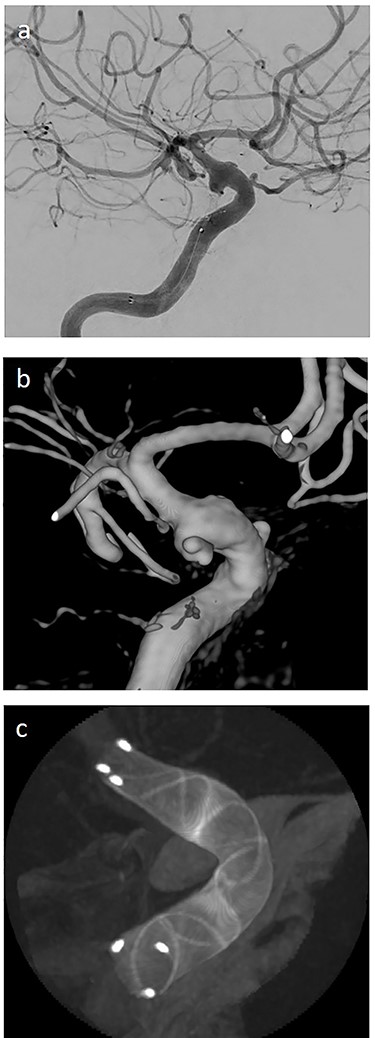

(a) lateral angiogram of left carotid artery showing ICA aneurysm before the second endovascular treatment; (b) Lateral view after implantation of two additional flow diverters (2× Derivo®—4,5/20); (c) Lateral view after additional coil embolization (HydroSoft™ 2/3 and 2× 1,5/2).

On the next day (Day 9 post-op), the patient suffered from acute and devastating headaches, with screaming and enuresis. An emergency computed tomography (CT) was carried out and displayed a prepontine and retroclival subarachnoid hemorrhage (Hunt & Hess Grade I), (Fig. 2). For further evaluation, a digital subtraction angiography (DSA) was conducted, and it showed a pseudoaneurysm of ophthalmic1/supraclinoid2/C23 part of the left ICA, which was directly treated by a flow diverter (Derivo®—4,5/20), with remaining rest flow (Fig. 3). The patient was transferred to the ICU, transcranial doppler sonography was performed and revealed normal flow. In the following course, the patient suffered from Terson’s syndrome and hyponatremia due to SIADH, but after clinical improvement, was transferred back to normal station after 10 days of post-operative monitoring. Furthermore, the patient was plagued with cephalgia and nausea, which could not be compensated with analgetics and antiemetics. On the 20th post-operative day after the epileptic seizure with postictal vigilance reduction, an emergency CTA was conducted showing progressive SAH (Fig. 4) and a growing pseudoaneurysm as well as generalized vasospasm with posthemorrhagic hydrocephalus. For an emergency CSF diversion, an external ventricle drain was placed. The repeated DSA showed a growing false aneurysm which was treated with two additional flow diverters (2× Derivo®—4,5/20) as well as coiling (HydroSoft™ 2/3 and 2× 1,5/2) by endoleak (Fig. 5). The vasospasms were treated by an intraarterial spasmolysis (Fig. 6).